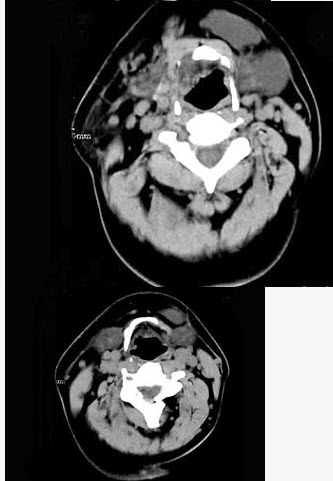

男,32岁,左侧下颌部肿块,CT如图所示,最可能的诊断是()。

A、造釉细胞瘤

B、颌骨囊肿

C、鳃裂囊肿

D、颈部淋巴管瘤

E、舌下腺囊肿

E